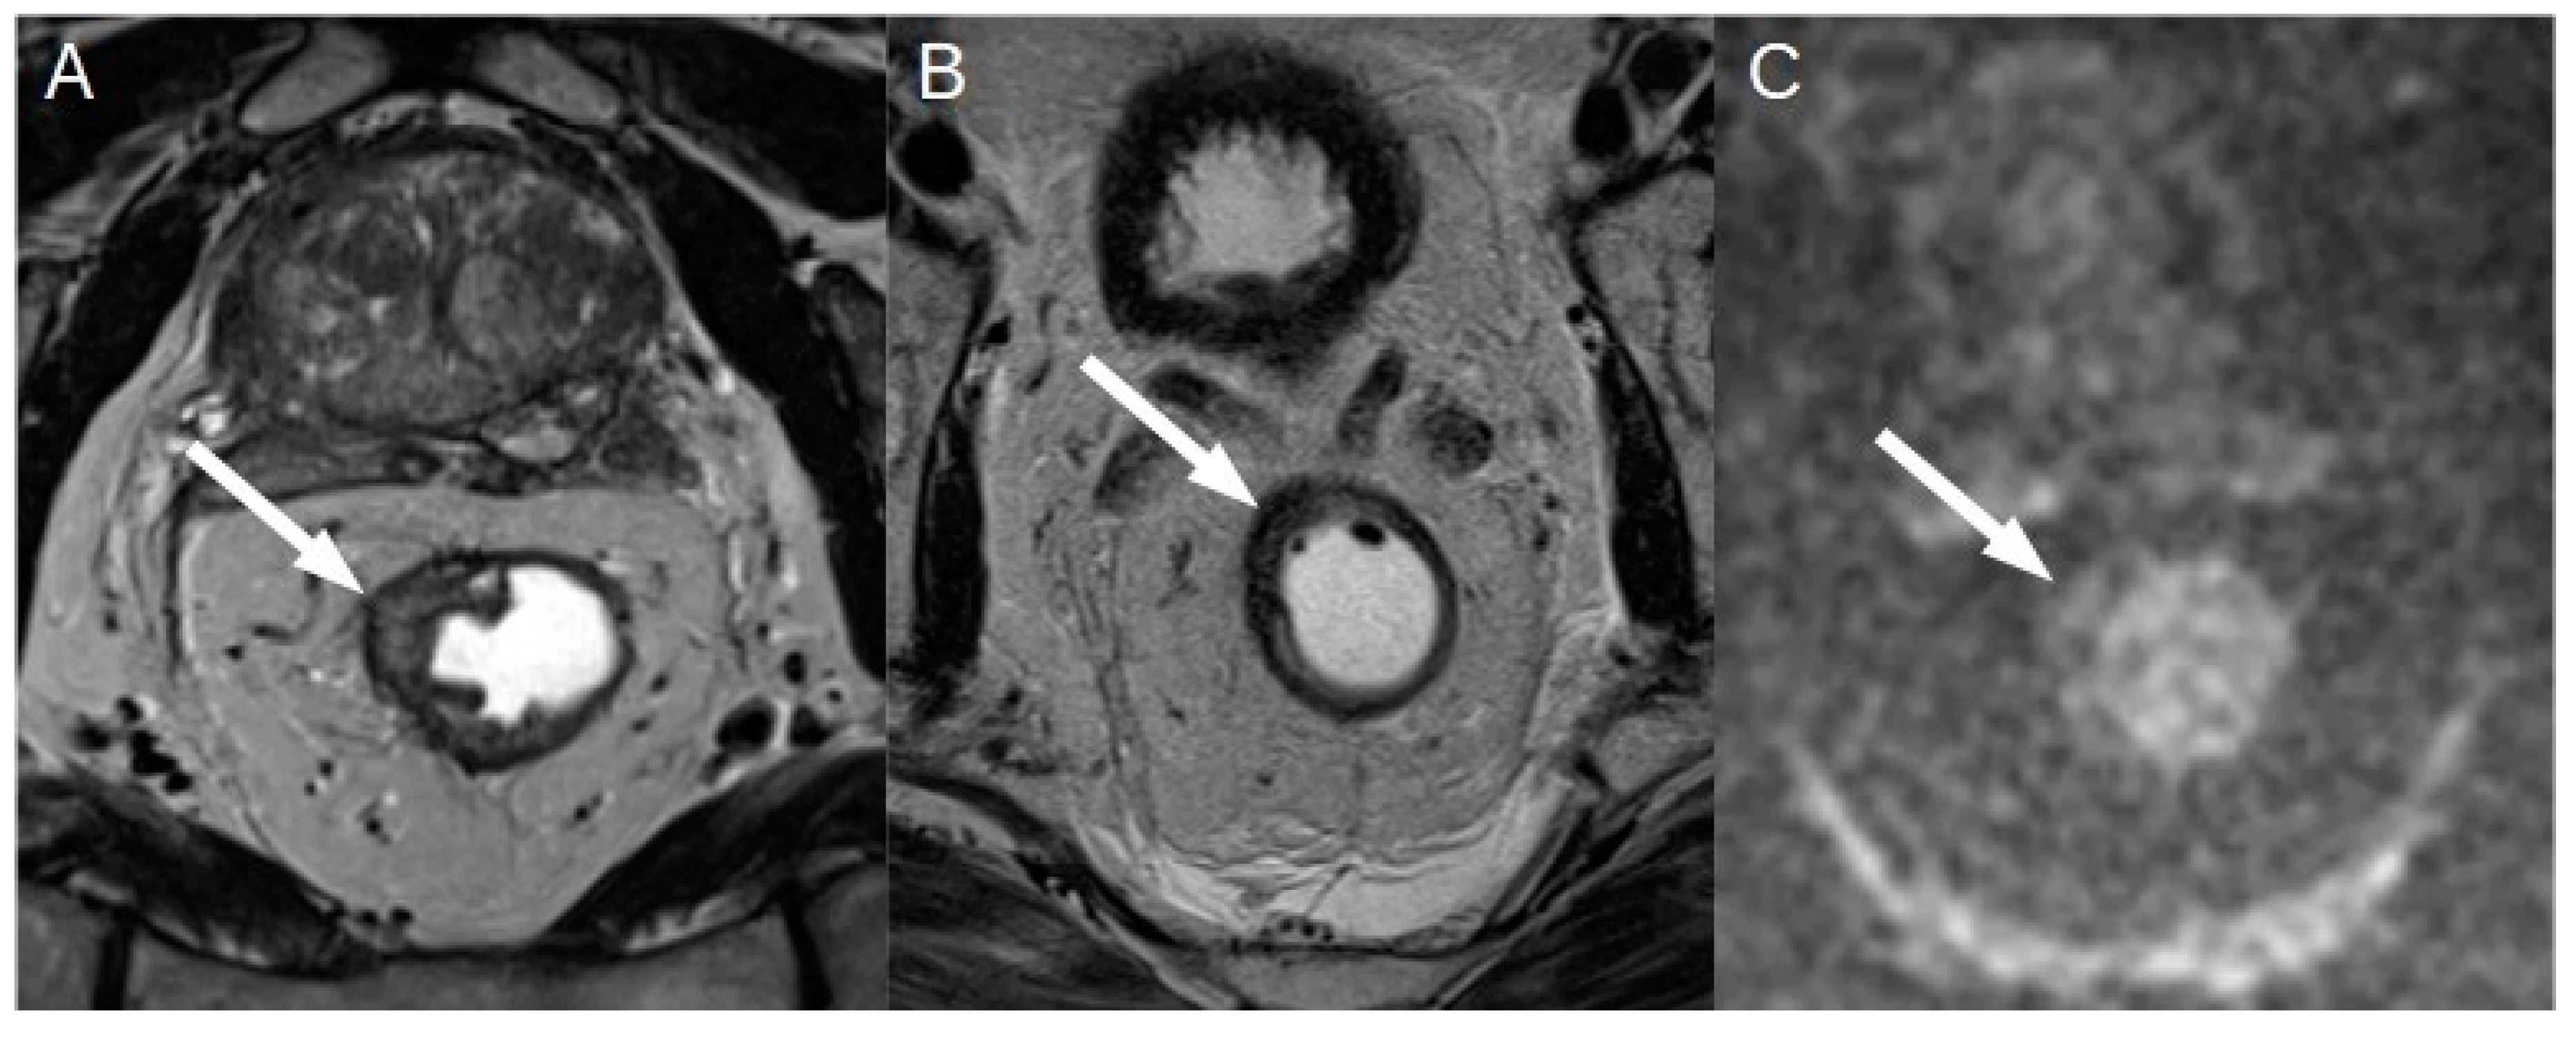

Initially, much of the research published about parametric imaging was focused on progress in acquisition methodology. This allowed to achieve numerous fast and robust mapping software, nowadays commercially available on the state-of-the-art CMR systems. And the evidence on the clinical value of CMR mapping from large clinical outcomes trials is rapidly growing. Thus, parametric mapping can be considered as a natural extension of comprehensive CMR protocols for a deep and quantitative myocardial assessment (Messroghli et al., 2017). Moreover, thanks to technological improvement, it is now possible to analyze the entire left ventricular myocardium with a global or segmental that showed the intrinsic advantage of higher sensitivity [Figure 3] (Meloni, Gargani, et al., 2023; Meloni, Pistoia, et al., 2023; Pepe et al., 2022).

The main limitation for spreading the mapping techniques in the routine clinical and research arena is due to its high reliance on the single scanner, on the type of sequence used and on imaging acquisition modality. This is the reason why normal reference values based on sex and age are recommended for each center considering that these parameters can be partially influenced by age and sex (Meloni et al., 2021, 2022; Messroghli et al., 2017) [Figure 4].

The need to a more in-depth characterization of heart function has led, in the last years, to the development of tissue tracking analysis. This technique provides a quantitative assessment of the global and regional kinetics of the myocardium, [Figure 3] giving adjunctive information about heart function other than those obtained by the grossly ejection fraction (EF) alone(J. Xu et al., 2022). In fact, the EF is a parameter of overall ventricular systolic function and does not provide information about regional myocardial kinetics and contractility nor allows evaluation of the diastole. Moreover, in many heart diseases, the EF is altered only late in the progression, leaving a diagnostic gap in asymptomatic or subclinical conditions. Since its introduction in the late 1980s, tissue tracking has been extensively developed and is now gaining popularity due to the development of software for fast and robust analysis and to research trends towards generating evidence of the adjunctive value of strain in early and differential diagnosis, risk stratification and prognosis determination of many heart diseases.(J. Xu et al., 2022) Recent evidence has given strength to this technique so that it is starting to be included in CMR assessment. As for mapping, the determination of normative values both for healthy subjects and disease specific population is important to avoid misdiagnosis.